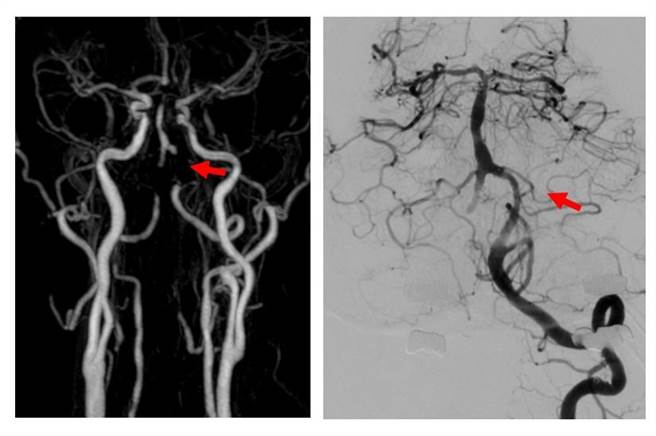

大里仁爱医院脑神经内科医师朱展麟指出,脑部核磁共振影像显示,邱先生的小脑、脑干及脑枕叶有零散的梗塞型中风病灶,两侧椎动脉有亚急性血栓导致的狭窄或阻塞,并发现有高血压、血液中叶酸及维他命B12偏低等情况。

邱先生1个月后回诊时,却发现有视力失焦的情形,转介到合作联盟的林口长庚医院,由神经放射科医师进一步检查发现,其两侧颅内椎动脉已完全阻塞。朱展麟说,脑干仅由椎动脉的细小分枝供应血流,有相当高的再中风风险。经双方讨论,邱先生决定放颅内椎动脉支架,手术进行十分顺利,2天后即出院。